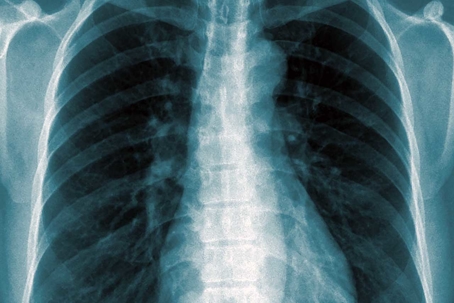

xray of chest

In 2009, the patient, Anna, was 18 months old and her father said that she was vomiting and may have had dehydration. The radiologist ordered an X-ray and diagnosed Anna with bronchiolitis v. atypical pneumonia and neglected to note and treat her enlarged heart. The myocarditis, an inflammation of heart tissue, developed into cardiac arrest and resulting brain damage. One of the lawyers at the firm representing Anna and her family noted that despite Anna now being 11, her actions and temperament are underdeveloped and she acts/reacts as a 4-year-old would; her injury caused severe and permanent neurological damage.